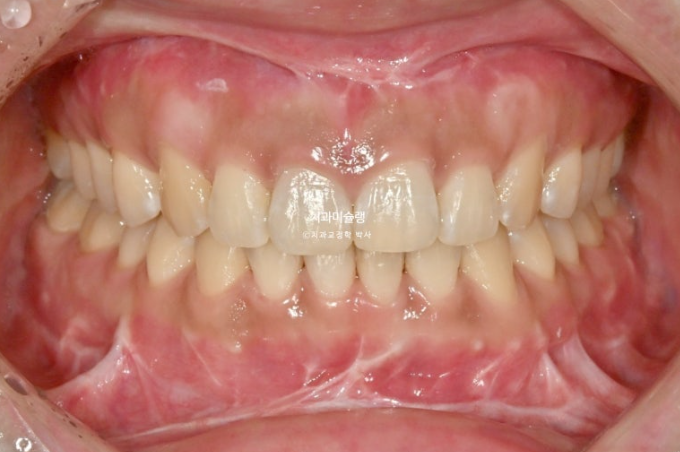

선수술 후 한달간의 회복기를 거쳐 25년 1월 본원에 내원했을 때의 교합 상태입니다.

25.01

아래 앞니 하나에 변색이 보입니다.

앞니 두 개는 나비치아 돌출이며

어금니 교합이 떠있습니다.

앞니에 배열이 삐뚤합니다.

이 정도의 상태라면 14개 장치 안에서 해결이 가능합니다.

즉 인비절라인 라이트로도 충분합니다.